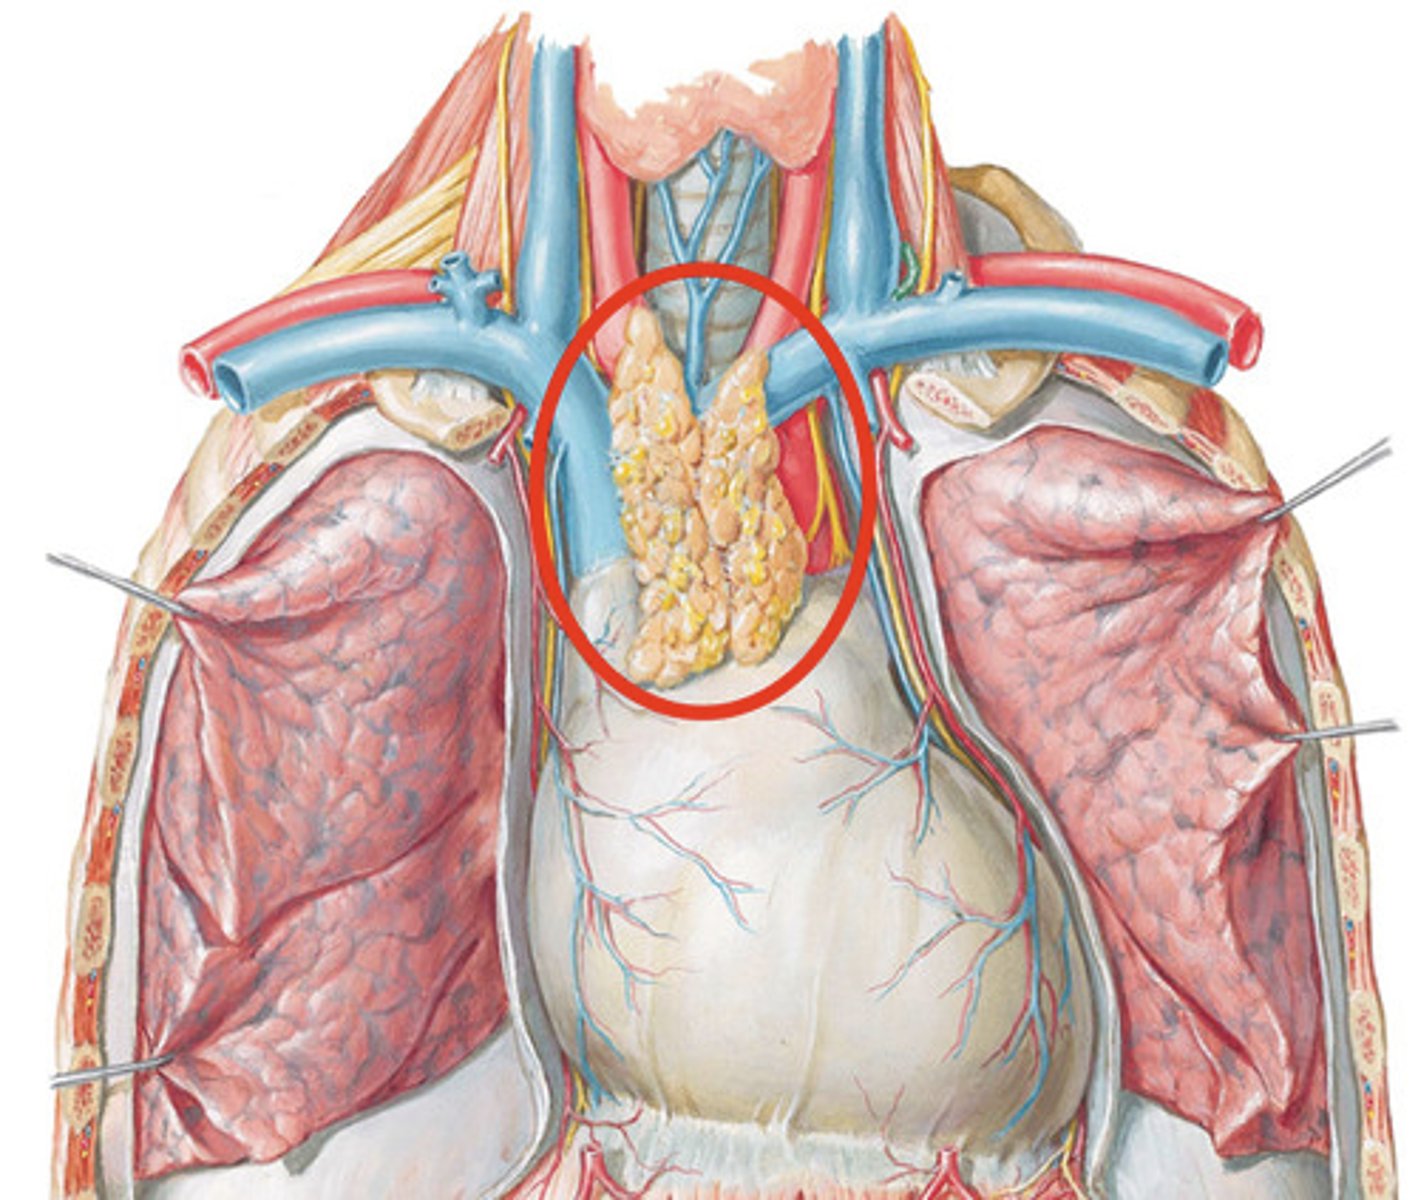

Thymus